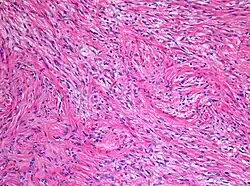

Makroskopisch handelt es sich um knollige, derbe Tumoren mit grau-weißer Schnittfläche, oft mit zystischen Anteilen. Feingeweblich handelt es sich um astrozytäre Tumoren, deren Tumorzellen charakteristische feine bipolare fibrilläre Fortsätze ausbilden und (namensgebend für den Tumor) als Pilozyten (Haarzellen) bezeichnet werden. Die mitotische Aktivität ist niedrig. Charakteristisch ist die relativ scharfe Abgrenzung gegenüber dem umgebenden Hirngewebe sowie ein biphasisches Wachstumsmuster, wobei sich faserreiche Abschnitte mit zahlreichen Rosenthal-Fasern und faserarme mikrozystisch aufgelockerte Bereiche mit sogenannten eosinophilen granulären Körpern abwechseln.